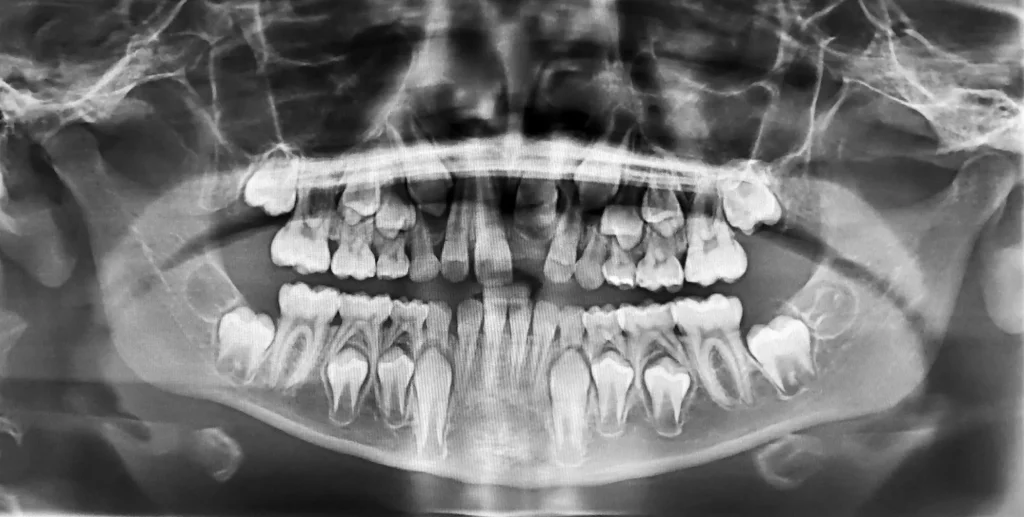

Rendgen zuba (ortopantomogram)

Ovo je često je prvi korak, jednom snimkom cijele čeljusti može se vidjeti postoji li skriveni zub u kosti i kakav je položaj njegovog korijena.

Preporuka je napraviti prvu panoramsku snimku oko 6. do 7. godine.

Na takvoj snimci može se razlučiti ima li prekobrojni zub zaseban korijen, kako je okrenut, te kod dvostrukog zuba koliko korijena ili pulpi ima.